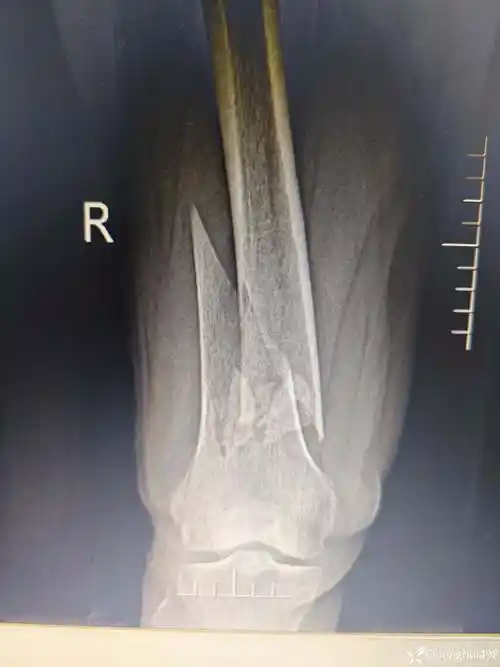

右股骨远端开放粉碎性骨折

股骨远端骨折(右侧髁上髁间)

股骨远端开放性粉碎性骨折